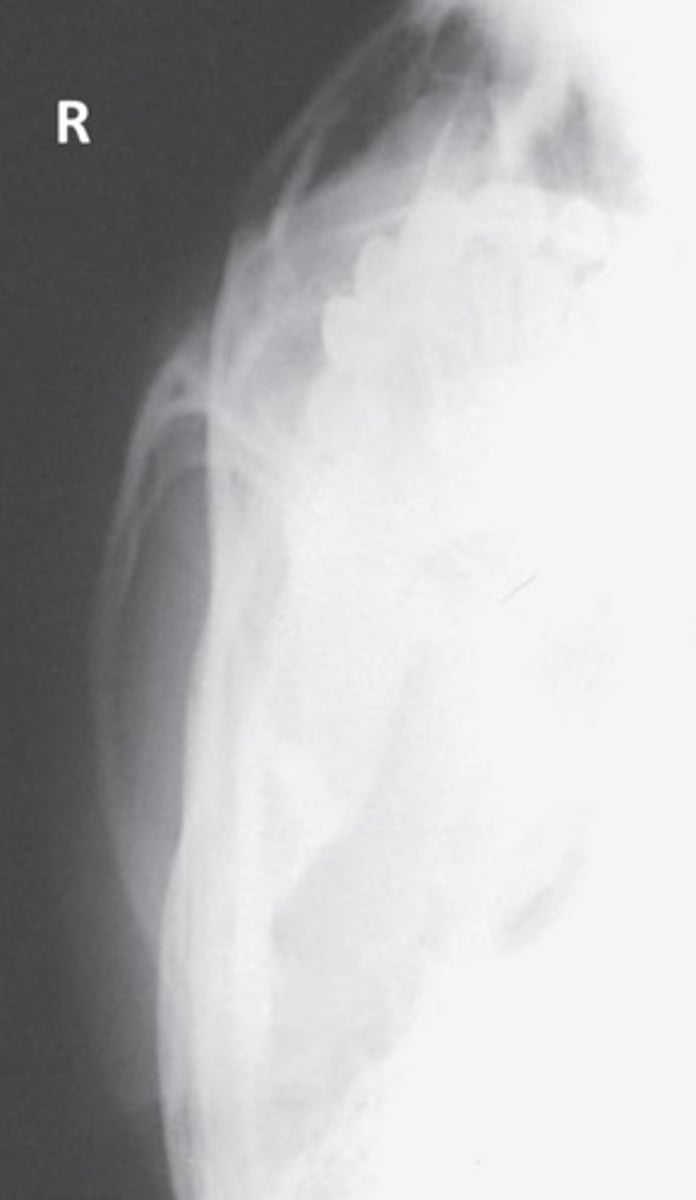

What projection and method is demonstrated?

Parietoacanthial (modified Waters)